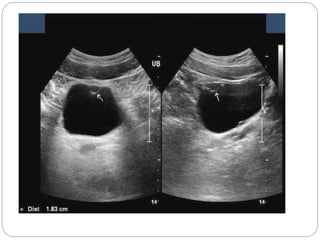

 Ultrasound demonstrates a simple

hypoechoic cyst; if the

characteristic 'gut-wall signature'

Abdominal x-ray of a patient with a duplication cyst. Note the

mass effect of the cyst pressing against the areas of colon

(arrows).